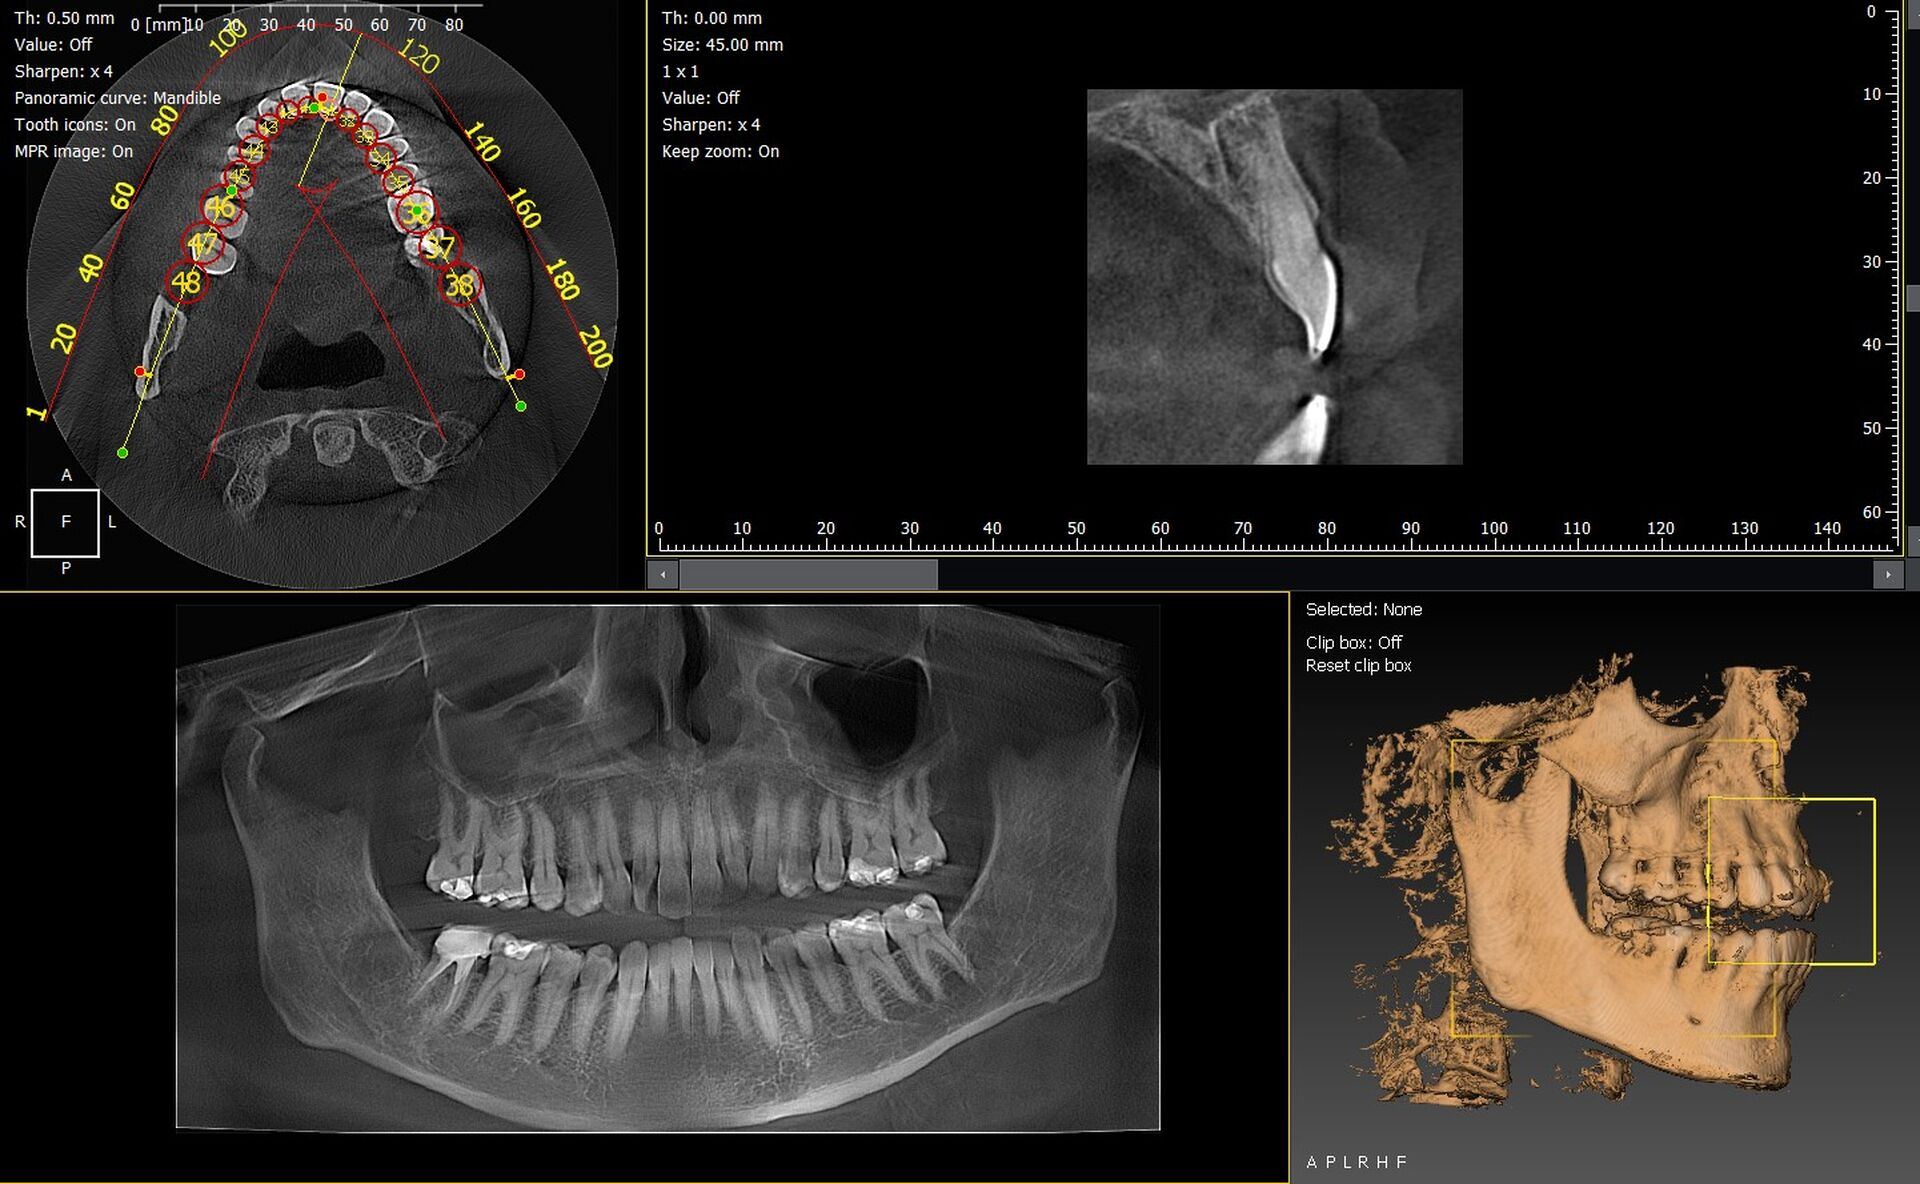

Les cabinets dentaires de Fréjus et du Var (83) investissent de plus en plus dans des solutions d’imagerie 3D performantes afin d’améliorer leurs diagnostics et de moderniser leur plateau technique. Parmi les équipements les plus fiables, les panoramiques CBCT 3D VistaVox de Dürr Dental et l’Owandy I-Max 3D se distinguent par leur qualité d’image, leur ergonomie et leur compatibilité avec les logiciels dentaires actuels.

VistaVox 3D : précision, volume optimisé et workflow fluide

Le VistaVox se distingue par :

• un volume de capture adapté à l’arcade dentaire,

• une excellente résolution idéale pour implantologie et endodontie,

• une dose réduite et contrôlée,

• un positionnement patient simple et rapide.

Owandy I-Max 3D : compact, polyvalent et économique en espace

L’Owandy I-Max 3D offre :

• un design mural ultra-compact,

• des protocoles 2D/3D rapides,

• une très bonne qualité d’image,

• une utilisation intuitive.